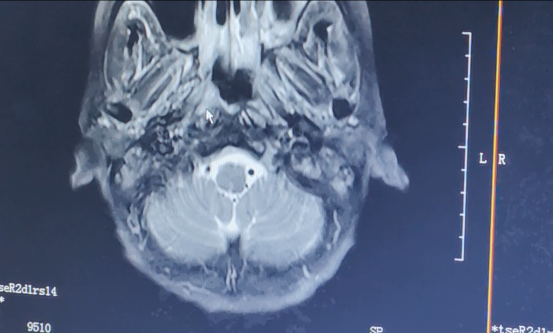

▲2019年6月影像結(jié)果

經(jīng)過(guò)兩周期治療后,阿芳的鼻咽病灶明顯縮小。隨后,醫(yī)生又為她進(jìn)行根治性放療。由于是二次放療,發(fā)生放療相關(guān)不良反應(yīng)的機(jī)會(huì)要明顯升高,比如口干、聽(tīng)力下降、張口困難,皮膚損傷等。為此,放療期間,醫(yī)生采用聯(lián)合三氧免疫治療、中醫(yī)中藥等輔助治療,減輕阿芳的不良反應(yīng),助力其順利完成放療。同時(shí),也利用免疫治療維持治療。